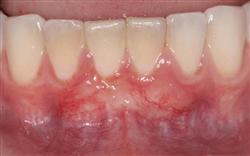

Normally gum tissue surrounds and protects the delicate roots of your teeth. Exposed tooth roots are prone to tooth decay, root canals, discoloration and actual jawbone loss. All of this can lead to tooth loss in advanced cases.

Functional Soft Tissue Grafting replaces the missing gum tissue and protects your teeth. For this reason, soft tissue grafting may be recommended even for back teeth.